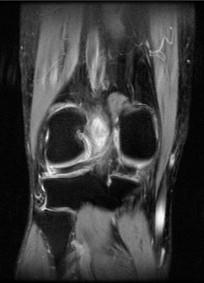

问题 男,50岁,膝关节侧方疼痛,请结合影像图像,选择最可能的诊断 ( )

选项 A、前十字韧带囊肿 B、膝关节腔积液 C、滑膜型关节结核 D、前十字韧带黏液样变性 E、化脓性关节炎

答案 D